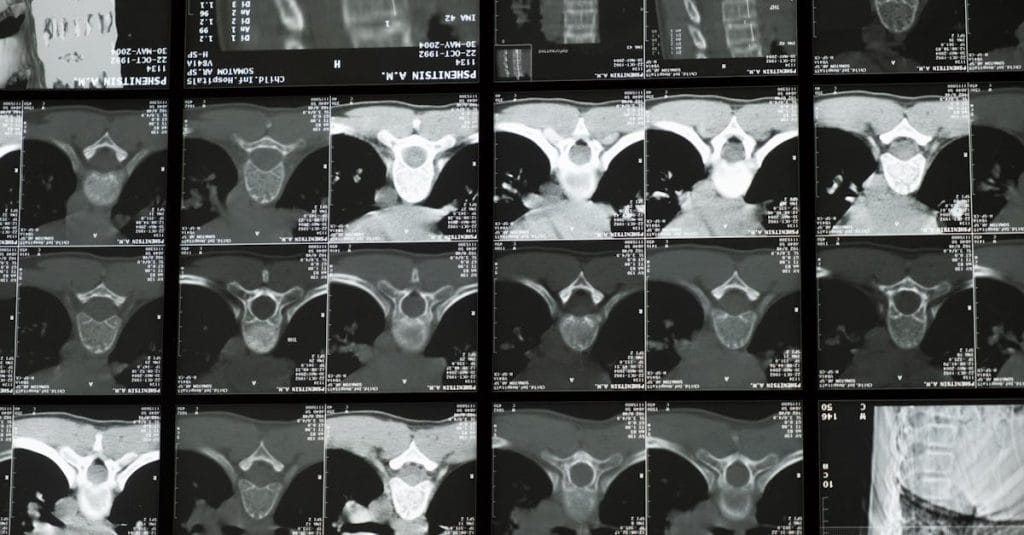

La décompression vertébrale repose sur des principes biomécaniques bien établis. Lorsqu’une pression excessive est exercée sur les disques intervertébraux, cela peut engendrer des douleurs, des bombements ou même des hernies discales. La décompression vise à créer un espace entre les vertèbres, permettant ainsi aux disques de se réhydrater et de retrouver leur forme naturelle.

Des études cliniques ont montré que cette méthode peut efficacement soulager la douleur et favoriser la régénération des tissus. En effet, en réduisant la pression sur les nerfs spinaux, la décompression neurovertébrale contribue à atténuer les symptômes associés, notamment les sensations de douleur irradiant vers les membres et les engourdissements.